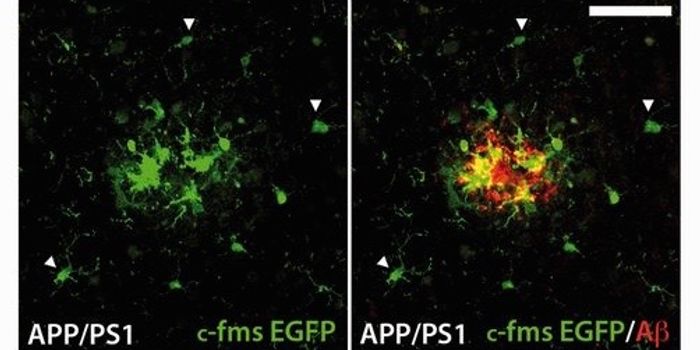

JUN 08, 2016NeuroscienceIt’s been known for a while that plaques of the protein amyloid beta are part of the pathology of Alzheimer’ ...

MAY 11, 2016ImmunologyThe brain’s immune system potentially could be harnessed to help clear amyloid plaques, which are a hallmark of Al ...